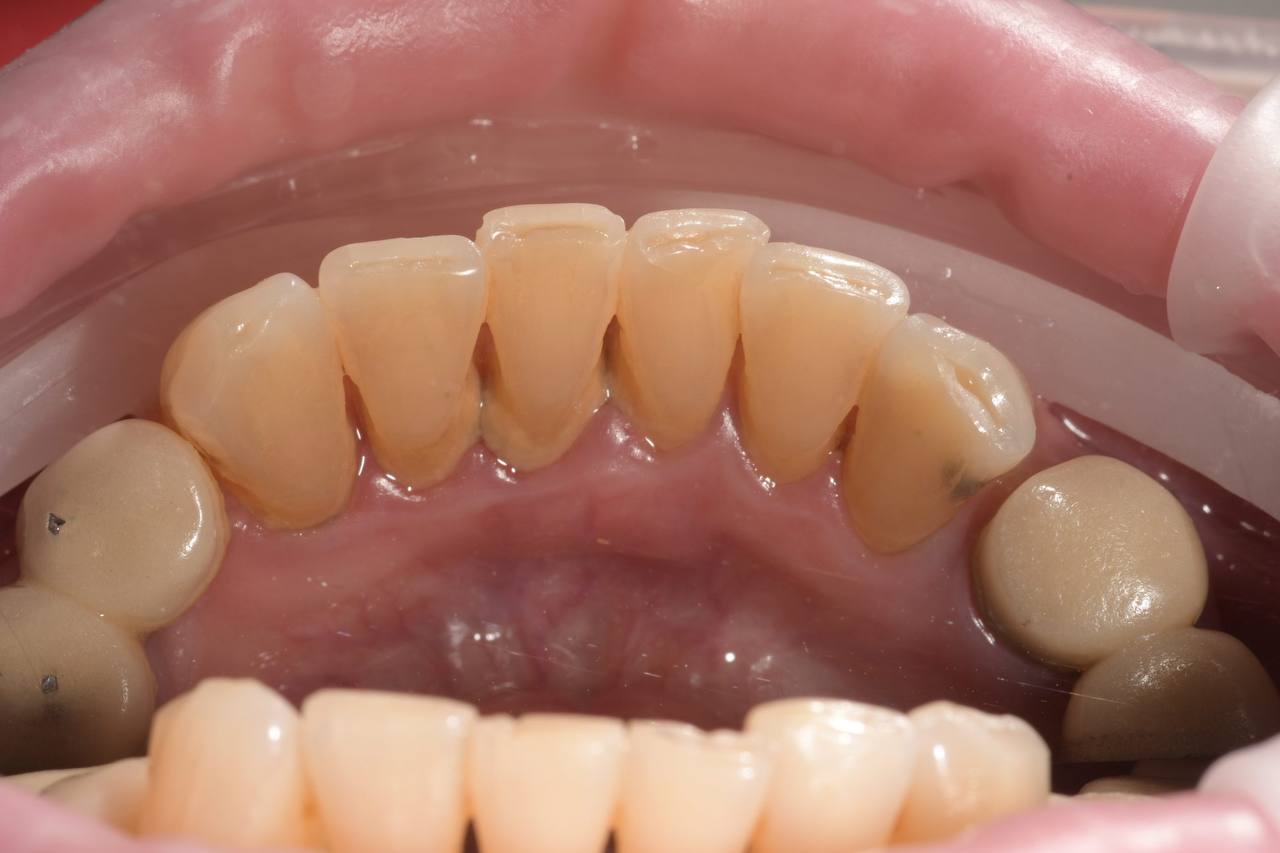

Після

Професійне чищення зубів

Професійне чищення зубів дає прекрасні результати, так як дозволяє не тільки зняти зубні відкладення, але й відполірувати зубні поверхні. Мікробам і харчовим забрудненням складніше прикріплятися до гладкої емалі, тому після процедури швидкість накопичення нальоту на зубах знижується.

Чищення зубів у стоматолога відрізняється максимальною ефективністю, оскільки у фахівця набагато кращий огляд ротової порожнини пацієнта, ніж у самого пацієнта. Стоматолог усуває наліт з усіх ділянок, включаючи ті, які пацієнт не бачить, або до яких не дістає.